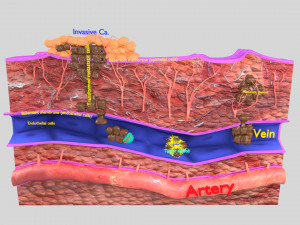

This is a 1:1 scaled model of right breast cut opened in sagittal plane to reveal its internal antomy and histology (schematic). The deeper parts and fascial layers are also depicted to give a very detailed approach to the model. The full layers starting from skin, nipple areola, till intercodtal muscles and ribs are also depicted.

breast mammary gland female chest wall anatomy human medical science reproductive genitalia muscle fascia milk nipple areola subcutaneous fatДо даного товару немає коментарів.